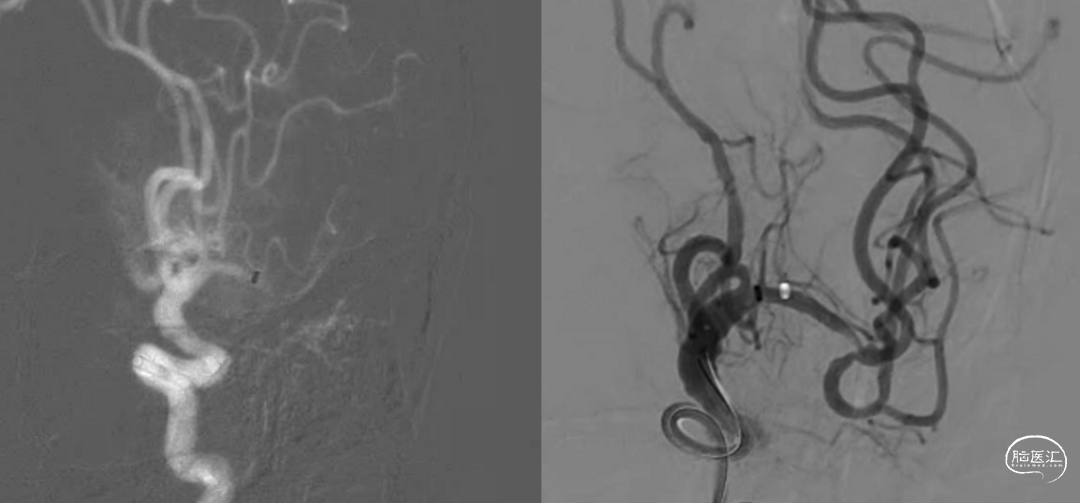

最后造影显示支架贴壁良好、支架内血运通畅、支架以远各级动脉分支显影良好。

对于颅内动脉慢性狭窄急性闭塞行逐级加奇SacSpeed® 2mm×9mm颅内球囊扩张可有效防止夹层形成,球扩成形良好后维持予欣维宁静脉抗板往往能维持责任病变的良好血运,可避免支架内急性血栓形成后闭塞的被动局面;对于部分出现管壁损伤的情况,使用开环支架修复损伤内膜、改善残余狭窄可能效果更好。

此病例中加奇SacSpeed® 2mm×9mm颅内球囊的优点非常明显:

a.加奇SacSpeed® 2mm×9mm颅内球囊充盈后显影性优良;

b.通过眼动脉弯等迂曲血管时柔顺性优良;

c.支架内后扩张操作过程中,加奇SacSpeed® 2mm×9mm颅内球囊进入支架、撤离支架均未见挂壁现象,安全性优良;

d.加奇SacSpeed® 2mm×9mm颅内球囊完全充盈后成形效果优良。